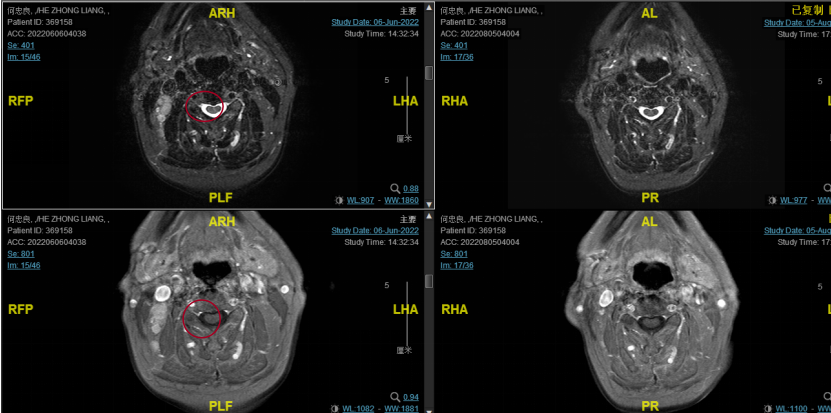

后患者至江苏省肿瘤医院放疗科就诊,2022-06-06完善头颅MR检查:

修正诊断:鼻咽癌T3N1M0,Ⅲ期。

2022-08-05(放疗近结束)复查MR,疗效评价:CR。鼻咽部肿物及咽后转移淋巴结颈部转移淋巴结均达到CR。